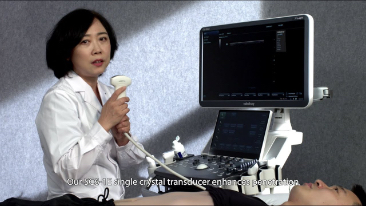

Las soluciones de imĂĄgenes generales de Resona de Mindray ayudan al personal clĂnico a realizar diagnĂłsticos y obtener resultados de tratamiento mĂĄs precisos y eficientes a travĂ©s de sondas para aplicaciones de subdivisiĂłn integrales y herramientas de aplicaciĂłn clĂnica eficientes.

Productos generales de generaciĂłn de imĂĄgenes